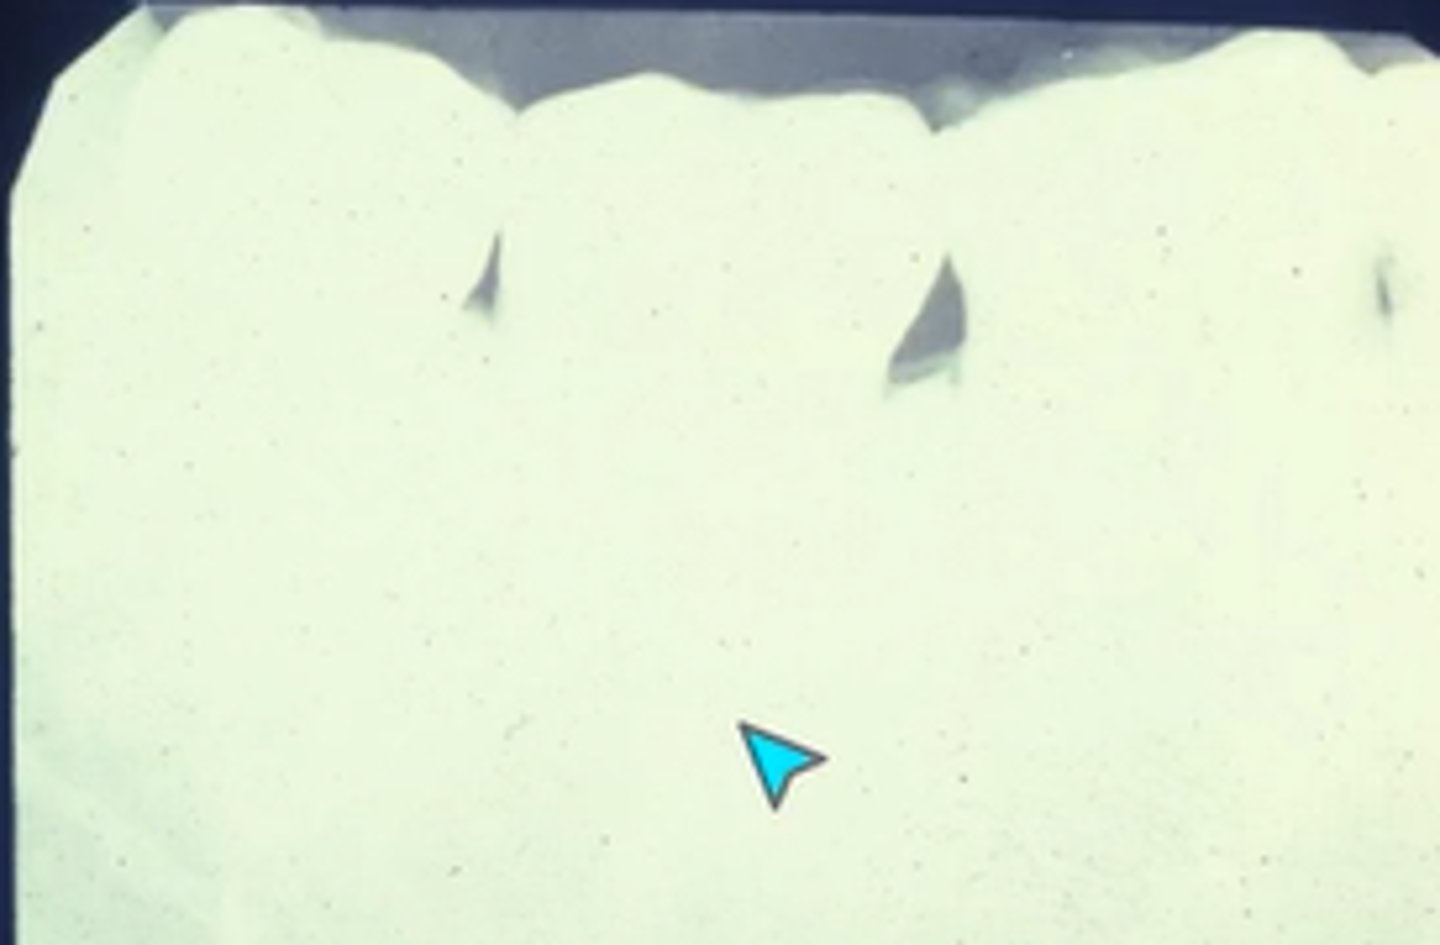

How do you explain the localized black area?

Light leak

What is this?

Film fog

What is film fog?

Unwanted darkness on the image, decreases value of radiograph